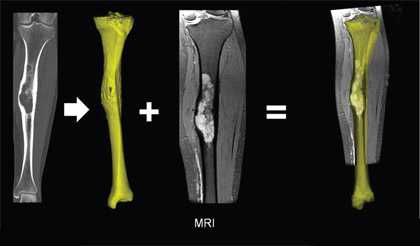

(Слева) Рисунок, аксиальная проекция: гемангиома тела позвонка с центральными массивными трабекулами. В аксиальной проекции эти трабекулы формируют рисунок в горошек, что довольно типично для подобного патологического очага. Рисунок: очаг, не выходящий за пределы тела позвонка, однако гемангиома может распространяться на задние элементы.

(Справа) КТ, аксиальная проекция, визуализируется гемангиома с массивными трабекулами, формирующими типичный рисунок в горошек. Гемангиома полностью занимает тело позвонка. (Слева) МРТ, сагиттальная проекция, режим T1: классическая гемангиома тела шейного позвонка. Визуализируются признаки массивных низкоинтенсивных трабекул в структуре гиперинтенсивной жировой стромы.

(Справа) МРТ, сагиттальная проекция, режим Т2: у этого же пациента визуализируется бревенчатый характер массивных вертикальных трабекул и гиперинтенсивность тела позвонка. Сигнал имеет типичные для гемангиомы характеристики в режимах Т1 и Т2. Изображение в режиме STIR не показано, однако для него характерно выпадение сигнала от жира и сигнал более низкой интенсивности от пораженною позвонка по сравнению с близлежащим позвонком. (Слева) МРТ, сагиттальная проекция. Режим Т1: гемангиома полностью занимает тело позвонка. Отчетливо визуализируются массивные низкоинтенсивные трабекулы, однако патологический очаг менее заметен, чем большинство гемангиом, поскольку не содержит большого количества жира.

(Справа) МРТ, сагиттальная проекция, режим Т2: у этого же пациента становится понятно насколько может быть затруднена визуализация атипичного очага с малым количеством жира. Трабекулярный рисунок едва различим на фоне небольшого количества близлежащего жира. Более типичная гемангиома визуализируется в области межсуставной части дужки.